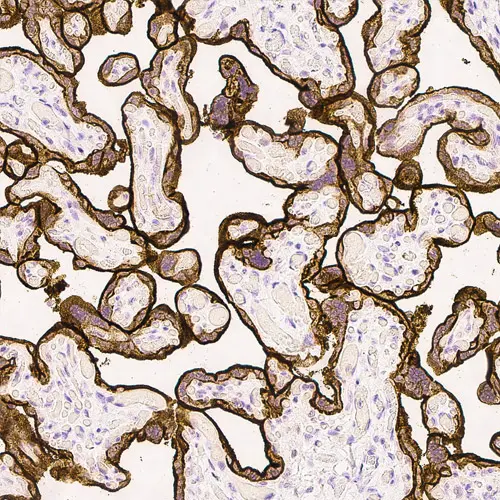

Human placenta: immunohistochemical staining for Epidermal Growth Factor Receptor. High expression of EGFR localized in the trophoblastic layer of the placental villi. Epidermal Growth Factor Receptor: clone EGFR.113

Le clone EGFR.25 est dirigé contre le domaine cytoplasmique de la molécule EGFR alors que le clone EGFR.113 est dirigé contre le domaine extracellulaire.